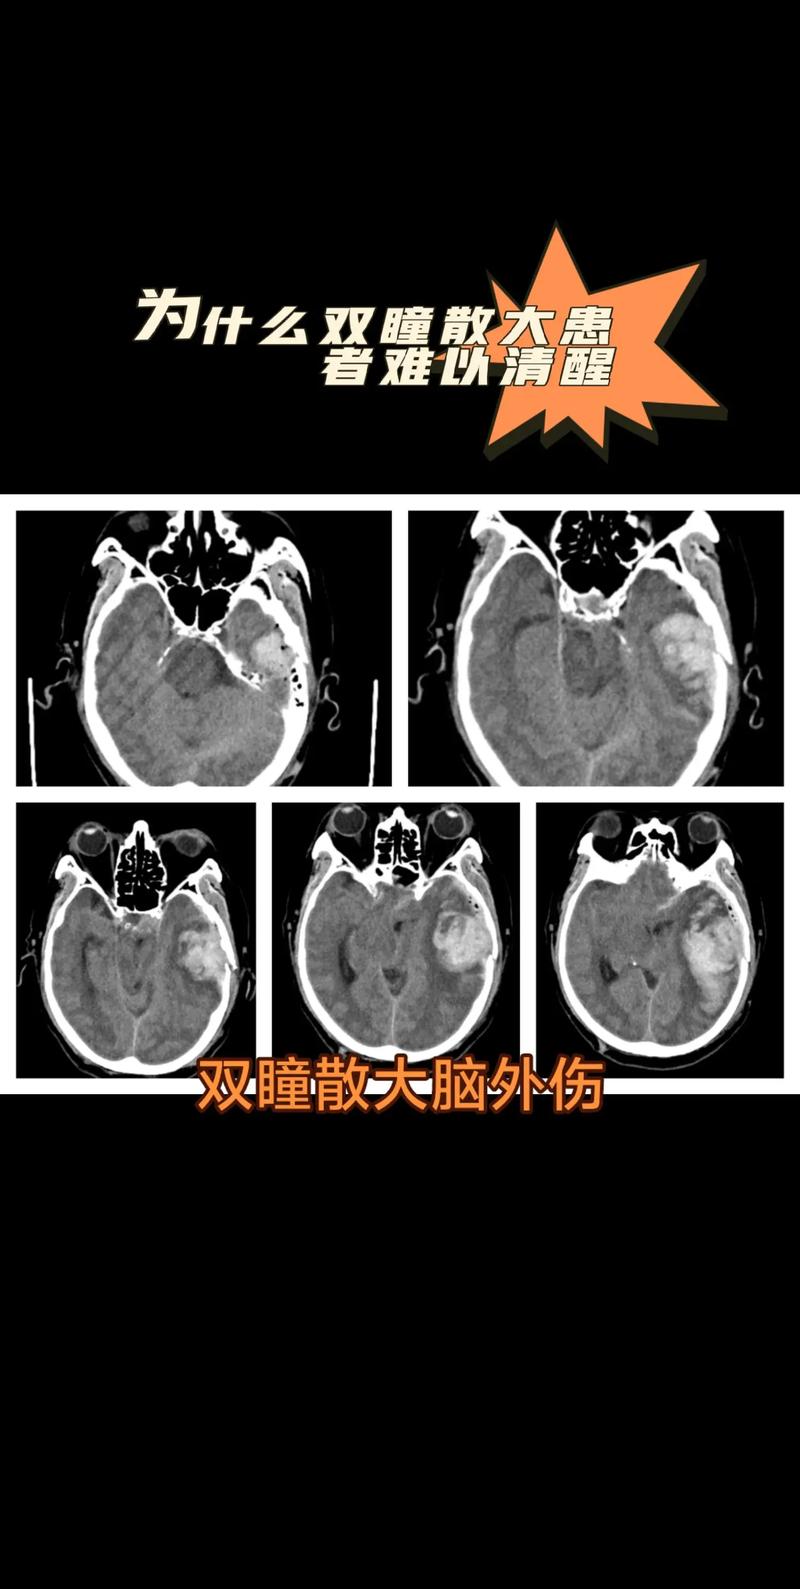

脑内水肿 + 脑梗 + 瞳孔放大 = 颅内压急剧升高,危及生命的脑疝形成。

瞳孔放大 (Dilated Pupil / 瞳孔散大)

- 是什么: 这是最危险、最关键的信号之一,它通常意味着一侧的瞳孔对光线的反应消失了。

- 这是“致命信号”: 我们的大脑底部有一条叫做“中脑”的结构,里面有一条重要的神经——动眼神经,它负责控制瞳孔的收缩,中脑还控制着我们的心跳、呼吸等基本生命中枢。

- 脑疝的形成: 当颅内压升高到极限时,肿胀的脑组织会像“汉堡肉”一样,被从高压区挤向低压区,最常见的挤压方向是从大脑半球向下,通过天幕裂孔(大脑和小脑之间的一个开口)向下压迫中脑,这个过程就叫做“脑疝”。

- 后果: 当中脑被挤压、移位时,首先被压迫和牵拉的就是动眼神经,这导致神经信号中断,瞳孔失去控制而放大,如果压迫继续加重,会直接破坏控制心跳和呼吸的中枢,导致心跳呼吸骤停,这是最致命的后果。